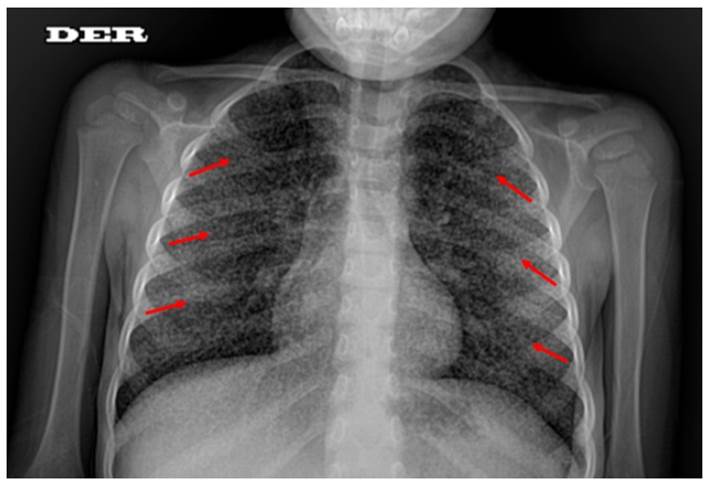

Varón de 4 años procedente de Florencia de Mora, Trujillo, La Libertad al norte del Perú; sin antecedentes clínicos ni epidemiológicos de importancia. Recibió vacuna bacilo de Calmette-Guérin (BCG) al nacer, de acuerdo al esquema nacional de vacunación. Presentó historia de linfadenopatías de 4 meses de evolución, se realizó biopsia de la lesión, la cual fue informada como linfadenitis crónica granulomatosa tuberculoide caseificante; concluyendo el diagnóstico de tuberculosis ganglionar, por lo cual se inició tratamiento con esquema sensible. Luego de recibir 13 dosis, por motivos desconocidos, abandonó el tratamiento. A los 2 meses, fue hospitalizado por recaída sintomática y reinició tratamiento con esquema sensible el cual volvió a abandonar tras 20 dosis. Tres meses después, presentó fiebre y malestar general, por lo que se le realizó una radiografía de tórax que evidenció compromiso bilateral sugestivo de afectación tipo miliar (Figura 1). Durante la hospitalización desarrolló tuberculosis meníngea e hidrocefalia. Debido al antecedente de abandono de tratamiento previo se solicitó cultivo BACTEC 960MGIT de aspirado gástrico con resultado positivo para M. tuberculosis y un estudio de sensibilidad en Agar en Placa y Genotype® MTBDR plus, identificándose como TB-MDR (Tabla 1), por lo cual se inició tratamiento con esquema: EZLfxKmEtoCs. La Cicloserina (Cs) se suspendió por posibilidad de reacción adversa neurológica. Se le realizó una derivación ventrículo-peritoneal, después de la cual se reinició la administración de Cs. Permaneció hospitalizado durante 4 meses con evolución favorable. Luego de 2 meses fue vuelto a evaluar por pediatra con mejoría clínica. El padre del paciente emitió su consentimiento para el uso de los datos en este reporte de caso.

Figura 1 Radiografía de tórax con patrón miliar, micronódulos de 1 a 3 mm distribuidos difusamente en ambos campos pulmonares.